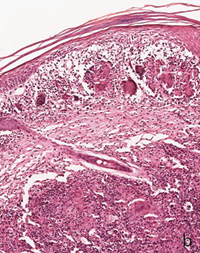

The infiltrates surrounded several neural bundles, which had dissociated perineurium (Figure 3,4).

Figure 3a A nerve in the center of the figure has dispersed perineurium and is surrounded by a giant cell. The peripheral infiltrate has many giant cells with numerous nuclei, lymphocytes and eosinophils.

Figure 3b These nerves (lower right B) have no defined perineurium and are surrounded by diffuse infiltrate of macrophages, giant cells, lymphocytes and eosinophils.

Figure 3c These nerves have no defined perineurium and are surrounded by diffuse infiltrate of macrophages, giant cells, lymphocytes and eosinophils. Vacuolated macrophages seem to be endoneural.

Figure 3d This nerve does not show perineurium and is surrounded by prominent giant cells, but looks well preserved. A-D: HE. A, B: 16 X. C, D: 40 X.

Some giant cells and macrophages touched the nerve or penetrate the endoneurium and distorted neural architecture (Figures 3,4). Other cutaneous nerves were located at the center of the infiltrate and looked well preserved (Figure 5).